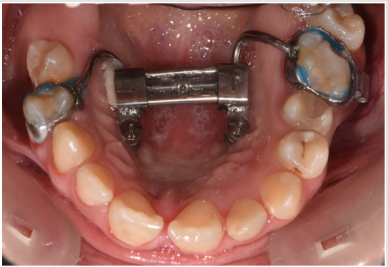

A female patient presented in our office for a consult. Her oral hygiene status needed improvement especially in the frontal upper area. Intraoral photographs reveal that in the transversal plane she had crossbite contacts between all the teeth and severe discrepancy between and the midline of the face the upper arch midline which was deviated to the right with almost the size of a lower incisor. In the sagittal plane she had canine class III on the right side and class I on the left side due to the rotated mandibular left canine and end to end to inverse overjet in the anterior region (Figures 3 & 4) and in the vertical plane, she had 1 to 2 mm of inverse overbite and bilateral open bite. Her upper right maxillary molars were absent and she presented moderate crowding in both upper and lower arch. The steps in the treatment plan were to expand the maxilla with the aid of a Hybrid Maxillary Expander followed by fixed appliances on the both Arches. In this case report, we present the results after the expansion of the maxilla and the processes that needed to be followed for the fabrication of the Hybrid Maxillary Expander. The first steps in the digital planning were clinical examination and intraoral scanning. The patient was referred to a radiological center for a CBCT. The intraoral scan and the CBCT were sent to the laboratory and analyzed for the implant planning. The mini screws were planned to be inserted in the anterior part of the palate, paramedian, this being an optimal area that has lower variability of bone thickness, a thinner mucosal layer and a lower density of blood vessels compared to the other [9].

The screws were planned to be angled toward the root of the incisor and as perpendicular as possible to the palatal surface for sufficient retention and efficiency [9]. After the acceptance of the digital planning by the medical team, a surgical guide was 3D printed. The Hybrid Maxillary Expander that was sent from the laboratory on a 3D printed cast consisted of two band sone on the second right upper bicuspid and another one on the first left upper molar, a median screw that was linked to the two paramedian mini-implants and two soldered arms that linked the median screw to the bands. The expander was bonded and in the same appointment, the mini implants were put in place using the printed surgical guide under local anesthesia. After the appointment, the patient was trained to activate the appliance twice a day, under a 90 degree turn until the screw reached the end. The patient was also informed about the apparition of a transitory diastema that was the sign that the suture had opened, and the treatment is successful. At the end of the expansion period, the appliance was kept in place for a 3-month period for healing of the mid-palatal suture that will deliver stability and low chance of relapse (Figures 7 & 8).